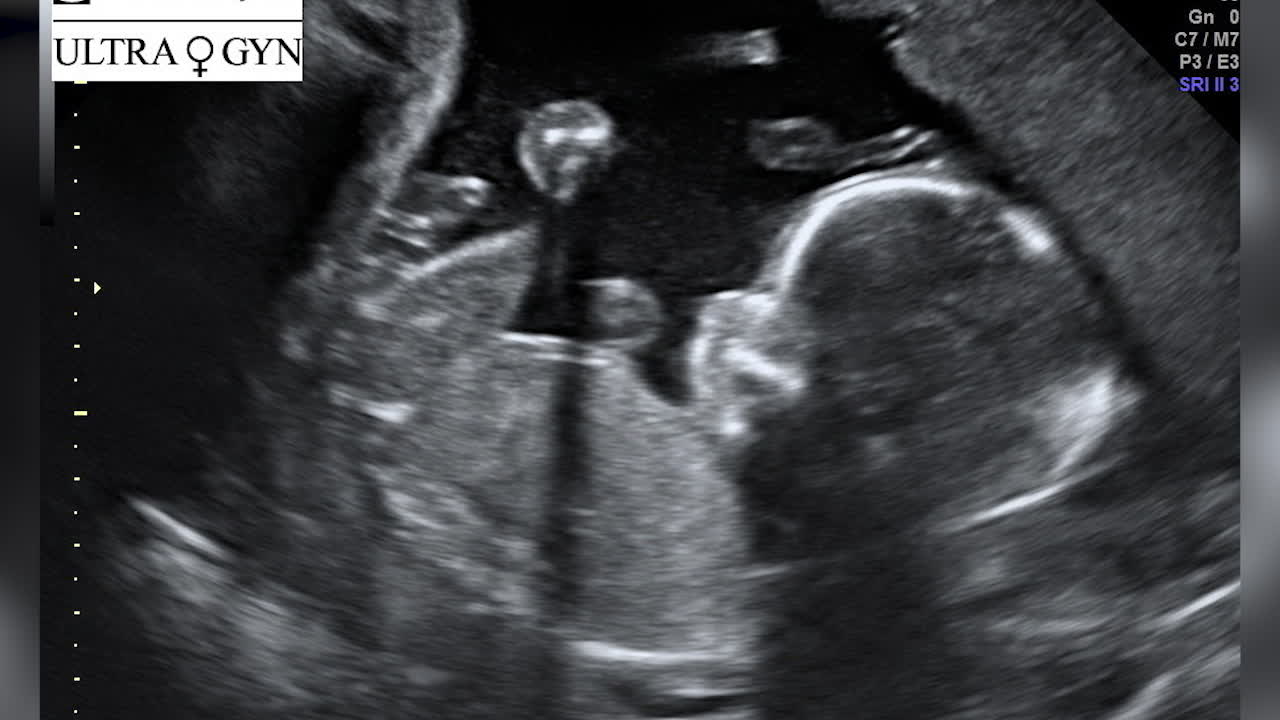

Via deras podd har lyssnarna fått följa deras resa mot barn.

– Han har en hejarklack som kommer vilja följa oss när han är utanför magen, säger Elsa.

– Vi har så många följare som är sjukt engagerade i den här ungen. Han har en massa cyberkompisar innan han ens existerar. Folk längtar efter honom utan att ens ha en relation till oss.